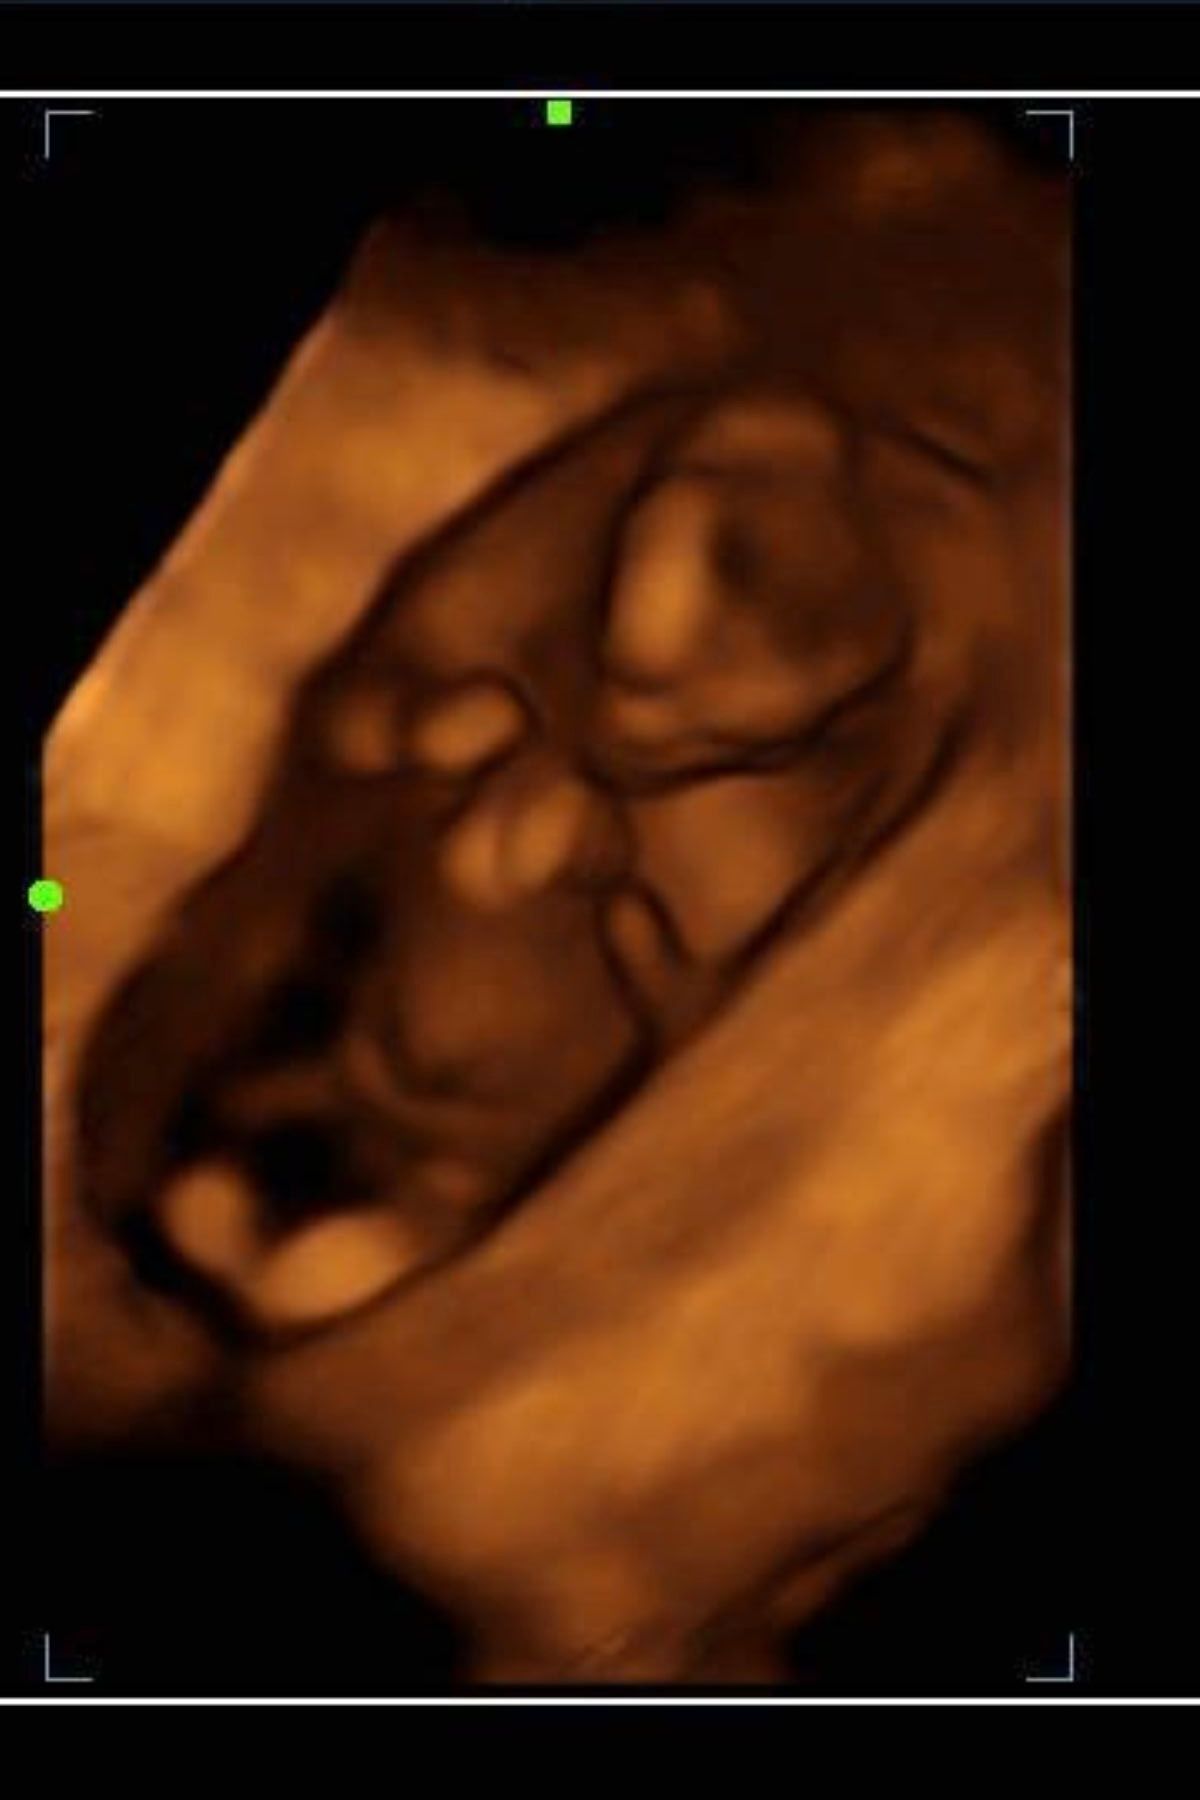

2d, 3d,4d & HD live

Enjoy a private, affordable ultrasound from the comfort of your home, perfect for moms between 7–41 weeks. Share the moment with loved ones by connecting directly to your TV for real-time viewing in 2D, 3D, or 4D. Ideal for baby showers or gender reveal parties!